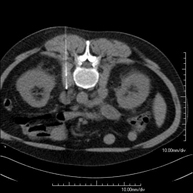

CT-guided abdominal FNA (fine needle aspiration)

It consists in obtaining a tissue sample from a specific lesion located in the abdominal cavity. This test is performed using local anaesthesia on the puncture area, which is administered with fine-gauge needles. The entire procedure is monitored using images obtained by computed tomography (CT) at various stages of the puncture, using CT fluoroscopy. After the test, the patient remains under observation in hospital for a few hours. Coagulation tests must be performed before the test.